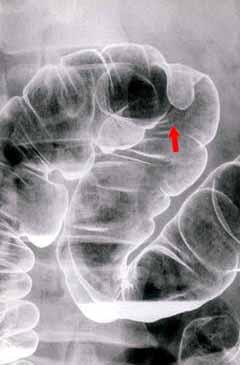

Lymphangioma in the transverse colon which demonstrated no change in its size and morphology for 5 years and 11 months.

Non-epithelial tumors/Lymphangioma

Location

Large intestine(Colon)/Transverse colon

X-ray

20 - 24